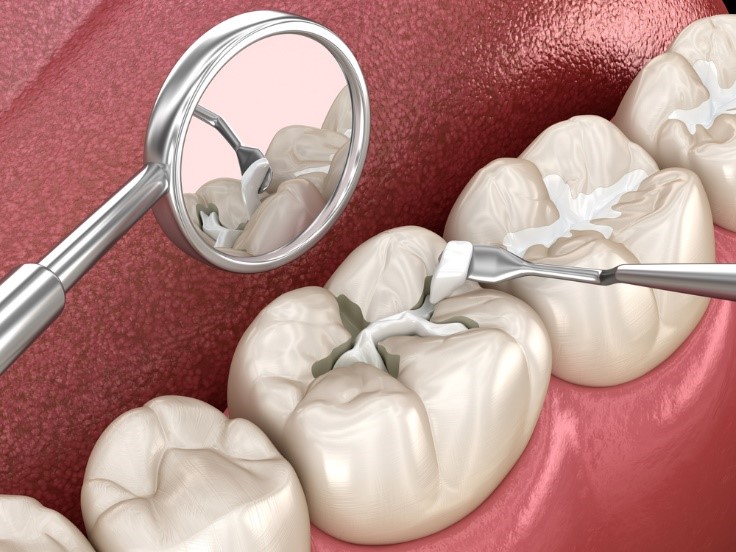

Tiến hành trám Composite: Bác sĩ đưa vật liệu Composite lên răng, tạo hình tỉ mỉ sao cho khớp với hình dáng răng thật. Sau đó dùng đèn Halogen/LED để làm đông cứng vật liệu.

Mài bóng và chỉnh khớp: Bước cuối cùng giúp bề mặt răng trơn láng, không gây cộm vướng khi ăn nhai.